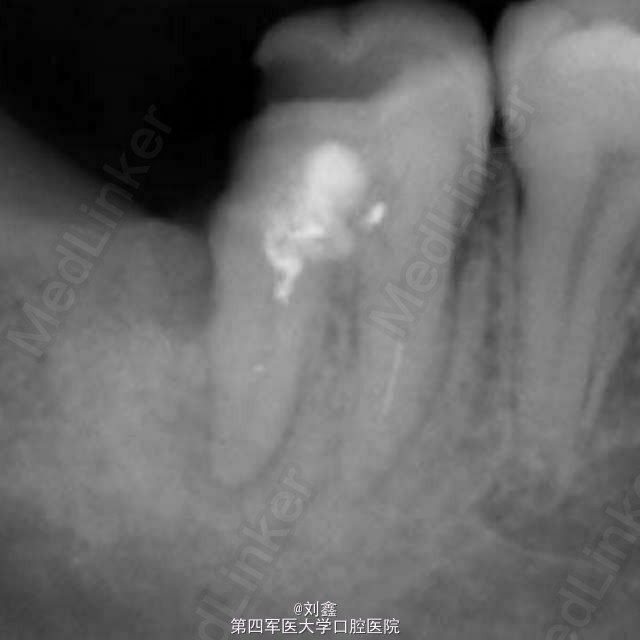

经典病例 根管内断针再治疗

患者女,29,右下后牙3年前于外院行治疗,冲填物脱落来我科。牙片示近中根有断针,遂行再治疗。

后牙根管再治疗

根管再治疗